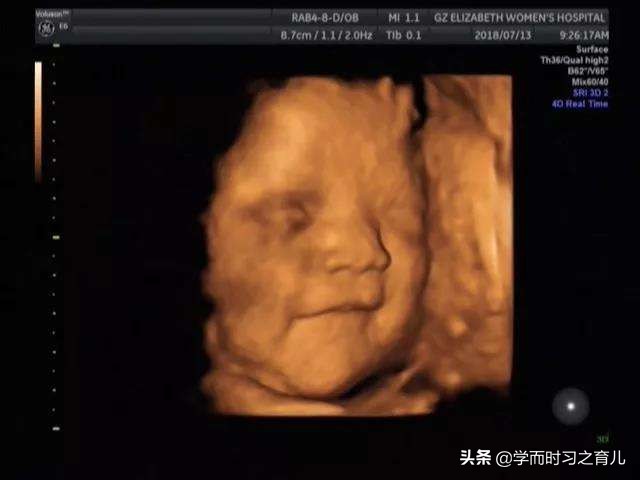

四维彩超通常可以排除胎宝宝大部分的畸形,很多孕妇都会以为四维彩超过关了,胎宝宝肯定就会健健康康得出生,其实在拿到四维彩超报告单的时候,准妈妈可以看到最后一行写的小字,大概意思就是不能排除胎儿所有的畸形以及随着胎儿的发育还有可能会出现异常。

虽然四维彩超已经是目前最先进的技术了,不仅可以检查胎儿的发育情况,还可以实时看到胎宝宝的各种动作,但这还是无法检查出胎儿所有的畸形,存在一定的局限性。

四维彩超一般只能检查出胎宝宝某个器官的结构形态有无异常,而不能证明这些结构的功能有无异常。因为有些结构的功能只有等胎宝宝出生以后才会显现出来。